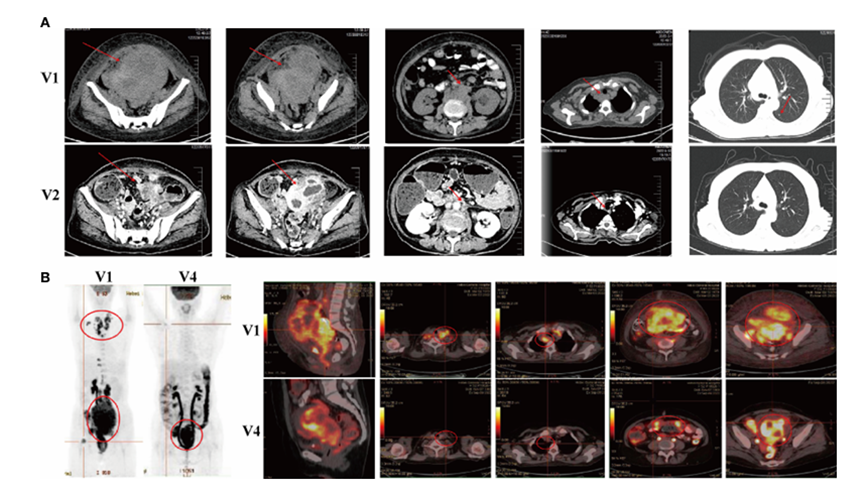

在第一个疗程的NK细胞免疫治疗后,患者就已经获得了部分缓解。她的体力、食欲和睡眠质量都有所改善。在第二个疗程的治疗后,PET-CT扫描显示子宫右侧肿块与治疗前相比显著缩小。颈部、纵隔、腹膜后和骨盆的多发淋巴结转移也消失。两个疗程后,患者的体能状态大大提升,生活质量显著改善。

图:治疗前后PET-CT结果,治疗后颈部、纵隔、腹膜后和骨盆的多发淋巴结转移消失了

图源:www.frontiersin.org